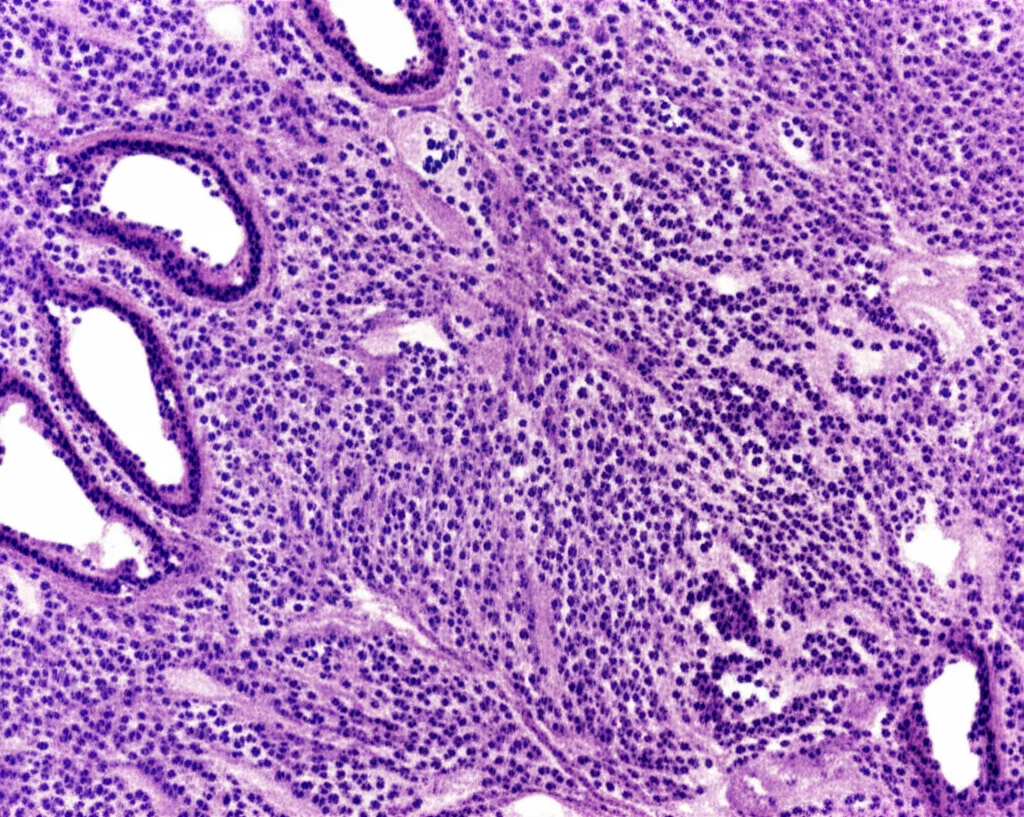

Immaginate una reazione eccessiva del sistema immunitario che porta alla formazione di piccoli agglomerati di cellule infiammatorie, chiamati granulomi non caseosi, in diversi organi. Questa, in soldoni, è la sarcoidosi. Una malattia multisistemica che può colpire chiunque, ma che predilige i polmoni e i linfonodi intratoracici (nell’80-90% dei casi). Il problema è che la sua presentazione clinica è incredibilmente variabile: da forme lievi che regrediscono spontaneamente a condizioni croniche, fibrosi o insufficienza d’organo irreversibile. Nei casi più gravi, quando coinvolge polmoni e cuore, può portare al decesso (circa il 7% dei casi), o a disabilità severe se attacca il sistema nervoso centrale (circa il 5%).

Quando i polmoni sono coinvolti, uno strumento diagnostico utile è la broncoscopia flessibile con aspirazione del liquido di lavaggio broncoalveolare (BAL). Analizzando questo liquido, in caso di sarcoidosi, si osserva spesso un aumento moderato della percentuale di linfociti (20-50%), anche se questo dato da solo non è specifico. Qui entra in gioco il rapporto tra due tipi di linfociti T: i CD4+ (helper) e i CD8+ (citotossici). Nella sarcoidosi, questo rapporto (R) tende ad aumentare a causa di un’eccessiva proliferazione dei linfociti T CD4+. Un valore di R ≥ 3.5 è stato proposto come soglia diagnostica, ma attenzione: la sua sensibilità e specificità sono variabili. Alcuni pazienti con sarcoidosi hanno un R < 3.5, e un R > 3.5 può trovarsi anche in altre patologie.